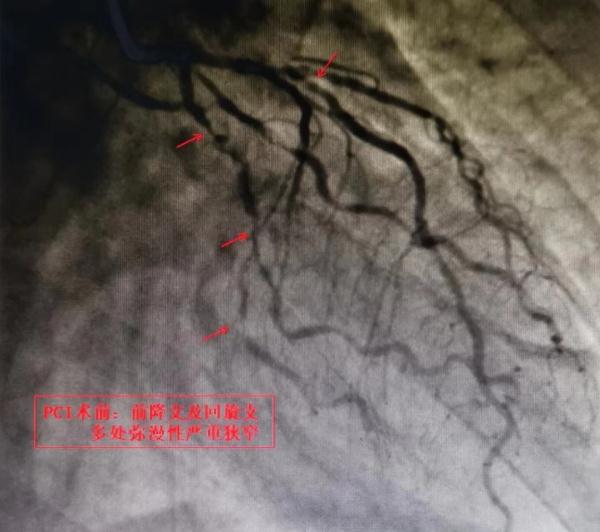

接诊的心内五病区主任容志毅在详细询问病史后,高度怀疑欧爷爷有心脏血管方面的疾病。入院后,经冠状动脉造影结果显示,患者心脏多支主要血管严重病变,左前降支、左回旋支皆有75%以上的弥漫性狭窄,严重狭窄处达95%。原来困扰欧阳爷爷半年之久的“胃病”竟然是“心病”。

△术前术后影像对比